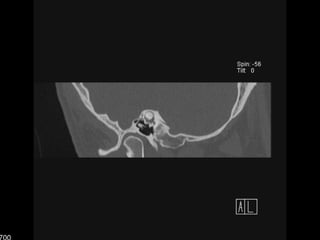

PöschlPlano en 45° oblicuo al plano coronal y sagitalSecciona el peñasco en el plano perpendicular a su ejeEl CSS aparece como un anillo con un arco entero de su pared superiorSe traza paralelo al curso del CSS

PÖSCHL